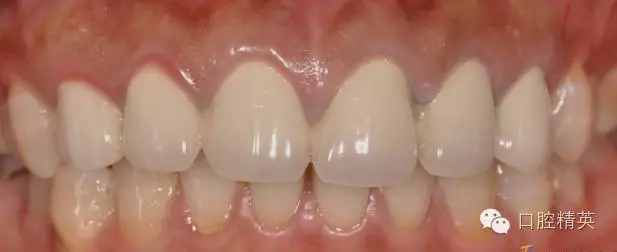

修復(fù)體完成后正面觀

修復(fù)體完成口內(nèi)照片